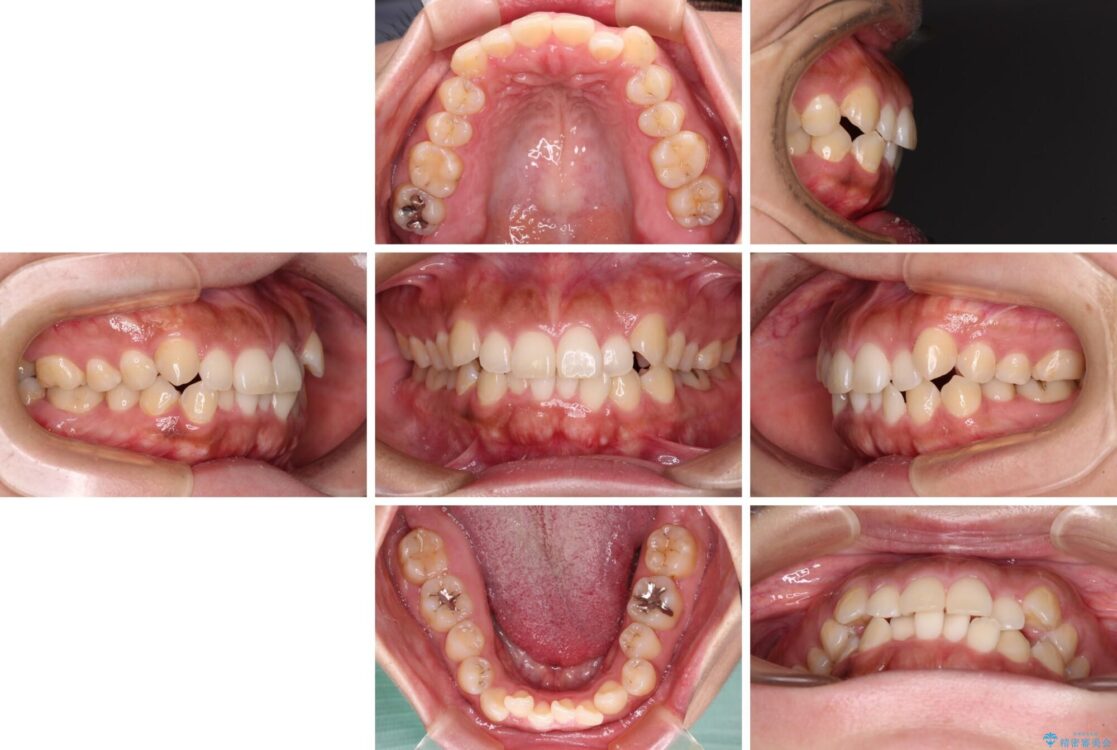

前歯の叢生と八重歯を気にして来院された患者様です。

治療前

• 【モニター】カリエール・ディスタライザーを併用した八重歯のインビザライン矯正 治療前画像